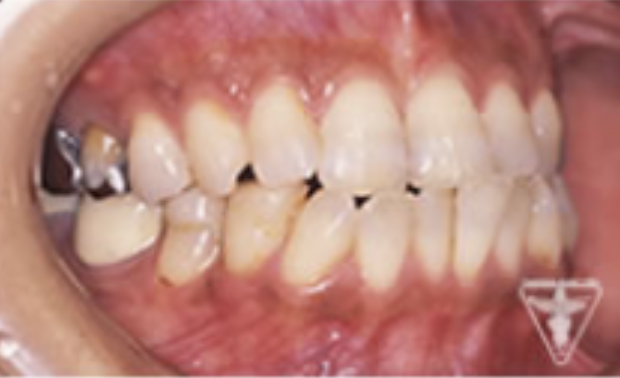

治療前

初診時の正面観・側方観・かみ合わせの面の状態を示します。

下の顎のずれがあるのを確認して下さい。